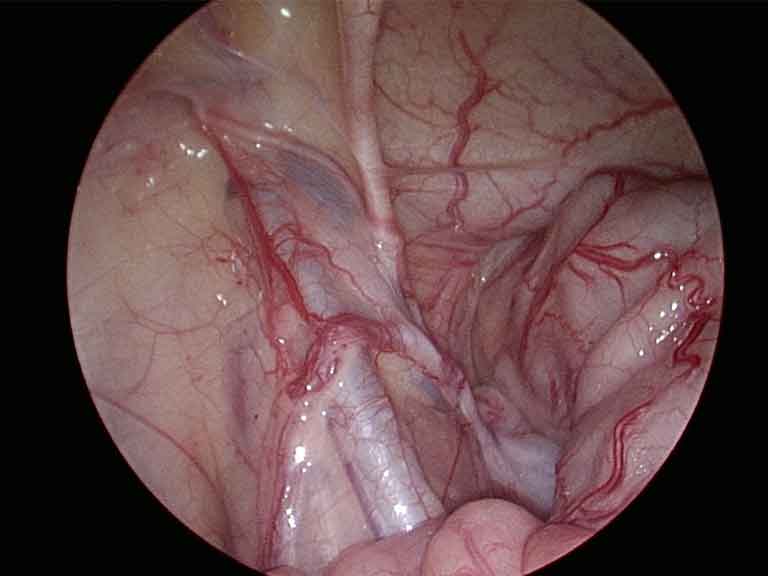

Laparoscopic view during abdominal wall hernia repair

Abdominal Wall Hernia

Laparoscopic Abdominal Wall Hernia Surgery

Keyhole repair of hernias in the abdominal wall — umbilical, ventral, incisional, and diaphragmatic hernias, as well as divarication of recti. A mesh is placed through small cuts to reinforce the abdominal wall without a large open wound.